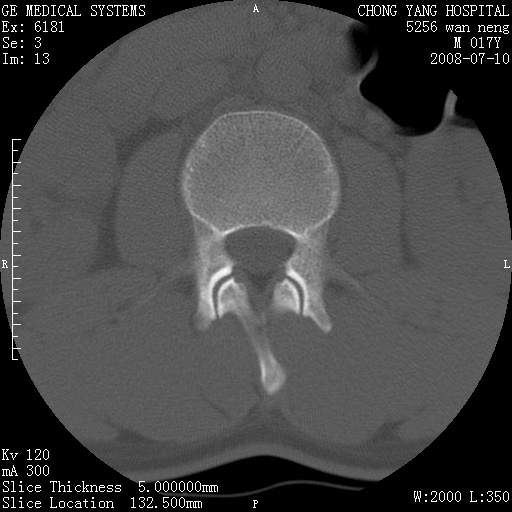

腰3、4椎弓崩裂

腰3、4椎弓不连

支持:腰3、4椎弓峡部崩裂。

腰3、4椎弓峡部不连

支持:腰3、4椎弓峡部崩解。

腰3、4,如受过外伤则为陈旧骨折,否则为骨质不连

图片漂亮,目前也只能看到腰3、4骨质不连

腰3、4椎弓峡部裂。

腰3、4椎弓峡部裂。支持

重建图像见多个椎弓峡部不连(不足为据),平扫未见异常。

支持腰3、4椎弓峡部崩裂。